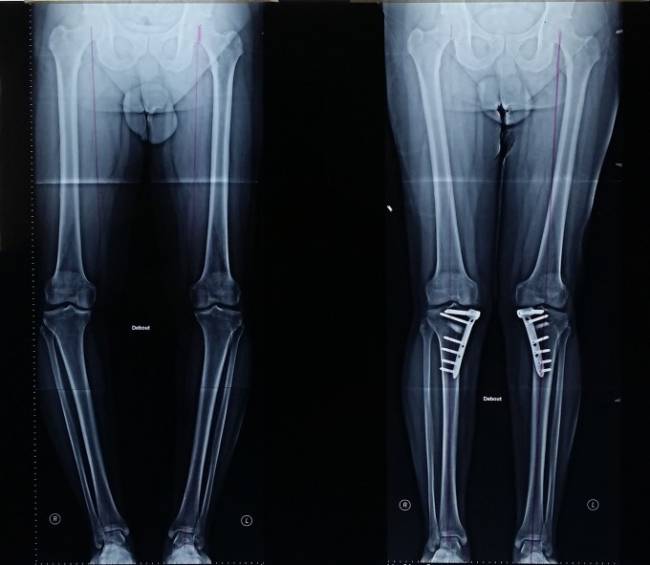

Хирургическое вмешательство с установкой на кости голени аппарата Илизарова.

Спустя 10 суток после установки начинается процесс коррекции кости, который заключается в компрессионном воздействии на кость регулярным подвинчиванием гаек в течение 1,5-2 месяцев.

Применение рекомендовано не ранее 14-летнего возраста. После снятия аппарата активные физические нагрузки исключены в течение 4-6 недель. Метод этот можно назвать традиционным, но, по мнению специалистов, его применение дает максимальный результат.

В том случае, если исправления искривления в ходе операции по остеотомии кости невозможно, то хирург принимает решение о применении аппарата Илизарова.

Аппарат Илизарова на ноге

Этот аппарат представляет собой некие кольца, что крепятся за счет спиц, что в свою очередь размещены непосредственно в костной ткани. Спицы аппарата Илизарова также выполняют функцию рычагов для растяжения или сжатия. Благодаря этому аппарату, врач способен зафиксировать кость в необходимом положении, для дальнейшего заживления. После того, как закрепили аппарат Илизарова на ноге, необходимо 2-4 дня передвигаться на костылях, но уже через месяц можно попробовать самостоятельное передвижение. Сам процесс коррекции будет начат уже через 10-15 дней после того, как операция была окончена. Для того чтобы все проходило по плану, необходимо постоянно подкручивать гайки, для того чтобы осуществлять контроль над изменением костных тканей. Естественно самостоятельно этим заниматься не стоит.

Врачи не рекомендуют ставить данный аппарат детям младше 14 лет, из-за плохого воздействия на психоэмоциональное состояние ребенка.

Данный аппарат необходимо носить около 2-3 месяцев, в случае успешного хода восстановительного процесса, пациент может продолжить лечение в домашних условиях.

Снятие аппарата Илизарова происходит в тот момент, когда врач рентгенолог, хирург и терапевт, на основании рентгенограммы сделают соответствующее заявление. Что касается послеоперационного периода после снятия аппарата Илизарова, то он заключается в отказе от физических нагрузок, при этом постепенно необходимо возобновлять двигательные функции, по рекомендации и плану врача.

Истинную кривизну можно качественно исправить с помощью хирургического вмешательства, которое проводят под общим наркозом. Это остеотомия, то есть рассечение костей в зоне дефекта. После их установления в правильном положении осуществляется фиксация аппаратом Илизарова, который носят до сращения тканей.

Приспособление представляет собой основу в виде колец и спицы, которые и вводят в кости. Аппарат устанавливается на 2 , 3 месяца, но с ним можно передвигаться, хотя и сначала на костылях.

Исправление положения костей начинается с 10-х суток. С этого момента подвижные детали аппарата подкручивают по разработанной врачом схеме. Специалист контролирует лечение на всем протяжении, в том числе с помощью фото ног и рентгена. После снятия аппарата восстановление продолжается несколько месяцев, и в нем пациента ждет немало ограничений.

Ортопедическая операция состоит в рассечении кости на участке ее деформации и затем фиксации конечностей в правильном положении с помощью специального аппарата (аппарат Елизарова). Аппарат представляет собой конструкцию из колец и спиц. Спицы размещаются в костной ткани и необходимы для того, чтобы кости срастались правильно. Ортопедическая операция длится 2-2,5 часа, после этого около 10 дней придется провести в клинике и еще 2-3 месяца носить аппарат Елизарова. Конструкцию не снимут до тех пор, пока кости не срастутся полностью, все это время прооперированный может самостоятельно передвигаться. После того, как конструкция будет снята, на ногах образуются небольшие ранки, они быстро заживают, оставляя едва заметные рубцы. Стоимость операции варьируется от 85 до 150 тысяч рублей в зависимости от сложности, сроков реабилитации и выбранной клиники.